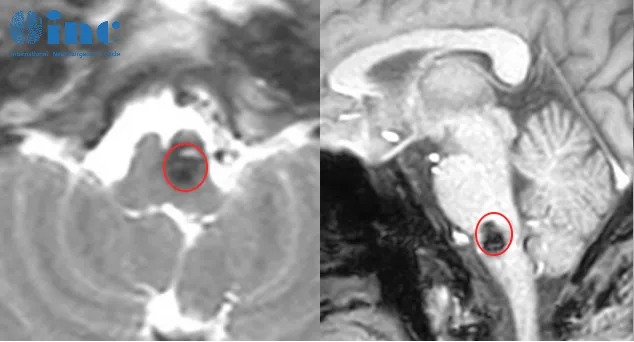

所有故事的起点,仅是一次手部麻木感。手麻在日常生活中极为普遍——可能是午睡时手臂受压,亦或是长时间打字后的短暂不适。很少有人会将其与脑部疾病相关联。然而,转折点出现在2021年。时年三十余岁、处于事业上升期的冯先生,因一次偶然的手部发麻就医检查,竟意外确诊为危险的脑干海绵状血管瘤。更令人担忧的是,这枚“不定时炸弹”恰好位于生命中枢——延髓。该区域负责调控呼吸、心跳等基本生命活动。一旦病灶破裂出血,将产生难以设想的后果。

脑干延髓海绵状血管瘤的手术入路需依据肿瘤具体形态特征选择,可选方案包括经髓帆入路、远外侧入路等,具体入路需根据患者个体情况及主刀医生的医学知识与经验制定。脑干延髓本身布满神经核团与传导束,而冯先生的血管瘤位置尤为刁钻,位于面听神经前下方与后组颅神经腹侧之间。

冯先生的手术方案确定为:1、乙状窦后入路延髓占位切除术;2、术中电生理监测(MEP+SEP)。2022年11月30日,该手术于苏州大学附属第四医院(苏州市独墅湖医院)如期实施,由巴特朗菲教授主刀。脑干海绵状血管瘤被顺利完整切除,未出现任何新发神经功能缺损。